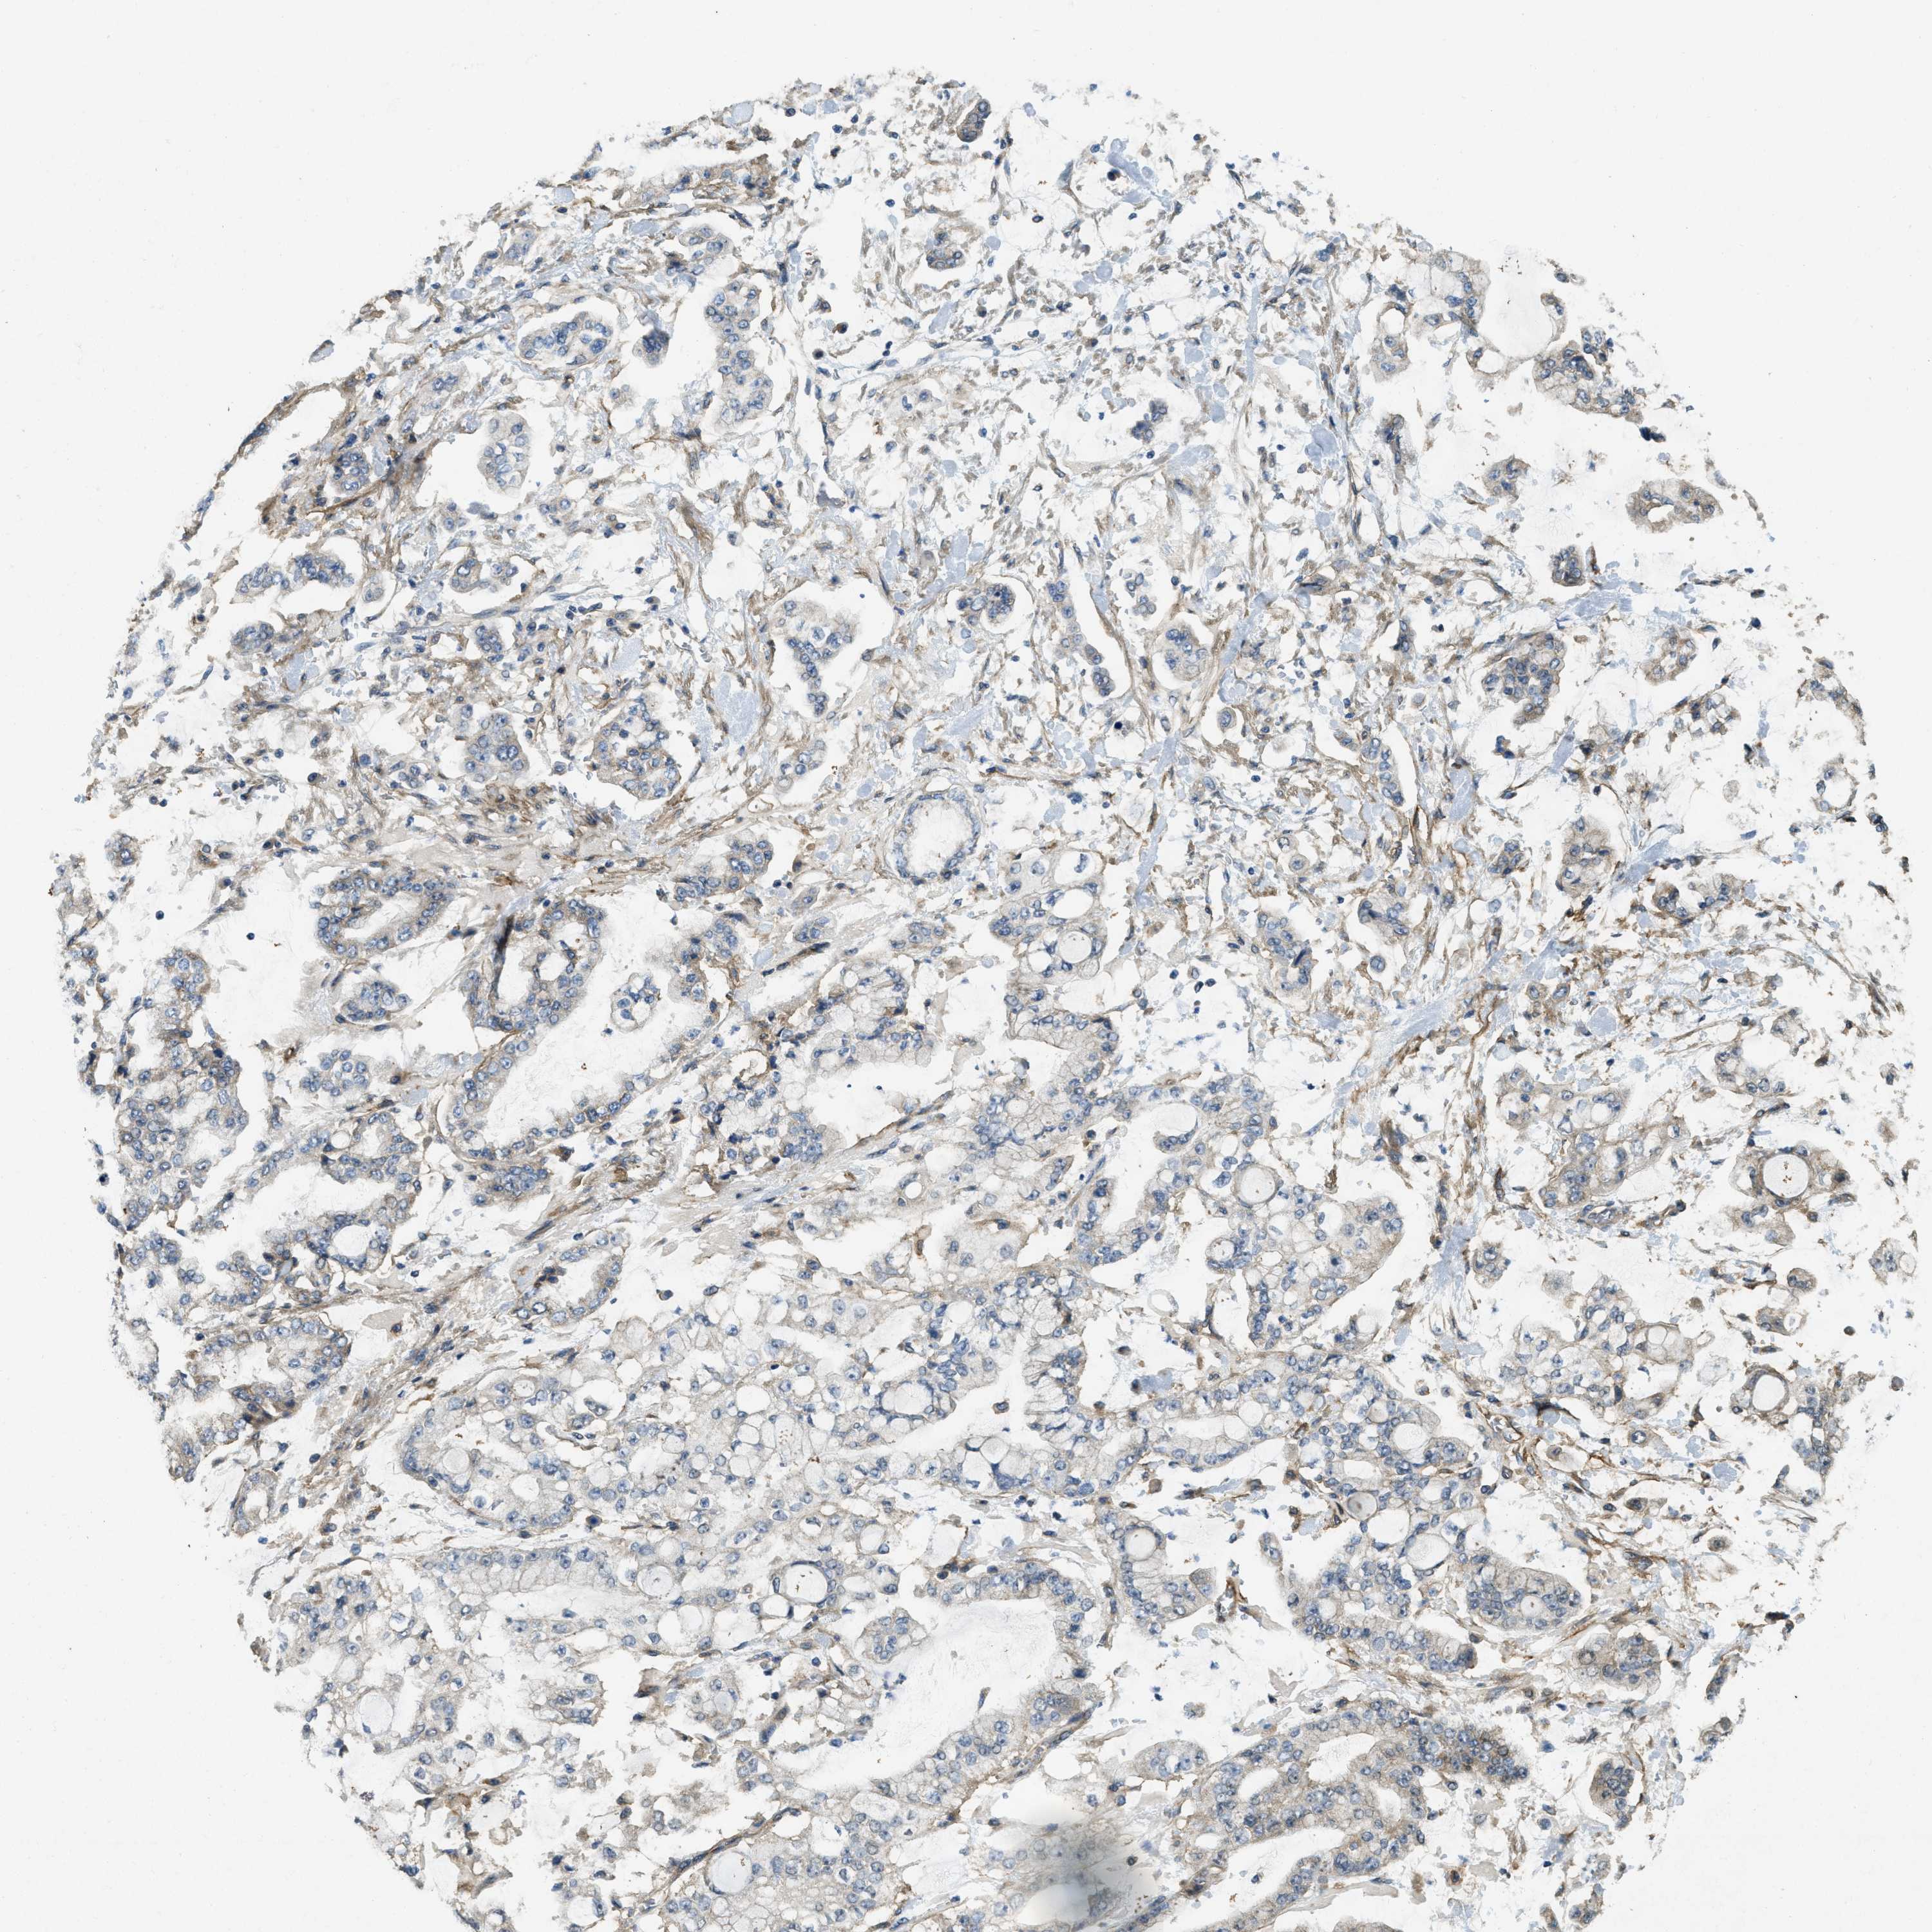

STOMACH CANCER - Protein expressioni

A mouse-over function shows sample information and annotation data. Click on an image to view it in a full screen mode. Samples can be filtered based on level of antibody staining by selecting one or several of the following categories: high, medium, low and not detected. The assay and annotation is described here.

Note that samples used for immunohistochemistry by the Human Protein Atlas do not correspond to samples in the TCGA dataset.

Antibody stainingi

Antibody staining in the annotated cell types in the current human tissue is reported as not detected, low, medium, or high, based on conventional immunohistochemistry profiling in selected tissues. This score is based on the combination of the staining intensity and fraction of stained cells.

Each image is clickable and will lead to virtual microscopy that enables deeper exploration of all samples and also displays staining intensity scores, fraction scores and subcellular localization as well as patient and tissue information for each sample.

Antibody HPA009285

Antibody HPA017139

Antibody CAB017826

Staining

High

Medium

Low

Not detected

Intensity

Strong

Moderate

Weak

Negative

Quantity

>75%

75%-25%

<25%

None

Location

Nuclear

Cytoplasmic/membranous

Cytoplasmic/membranous,nuclear

Adenocarcinoma, NOS

Adenocarcinoma, High grade